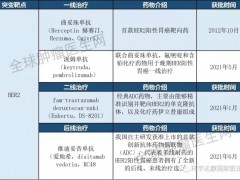

适合患者:NTRK1/2/3、ROS1或ALK基因重排突变的实体瘤

适合患者:只要存在NTRK融合,不限癌种

适合患者:晚期恶性实体瘤

适合患者:NTRK基因融合

适合患者:标准治疗失败或无标准治疗方案的晚期实体肿瘤患者

适合患者:晚期实体瘤患者

适合患者:晚期或转移性实体瘤